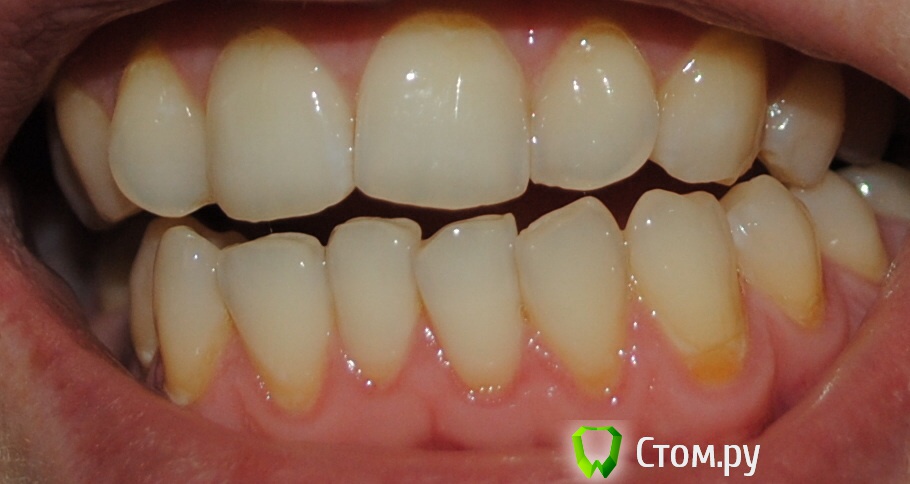

Алина-малина Опубликовано 29 января, 2014 Автор Поделиться Опубликовано 29 января, 2014 Здравствуйте,Выложите ФотоФото дефекта???Выкладываю) Ссылка на комментарий

Алина-малина Опубликовано 29 января, 2014 Автор Поделиться Опубликовано 29 января, 2014 И еще вот на всякий случай Ссылка на комментарий

red_butler Опубликовано 30 января, 2014 Поделиться Опубликовано 30 января, 2014 практически на всех что на фото, выглядят как белесые пятна Ссылка на комментарий